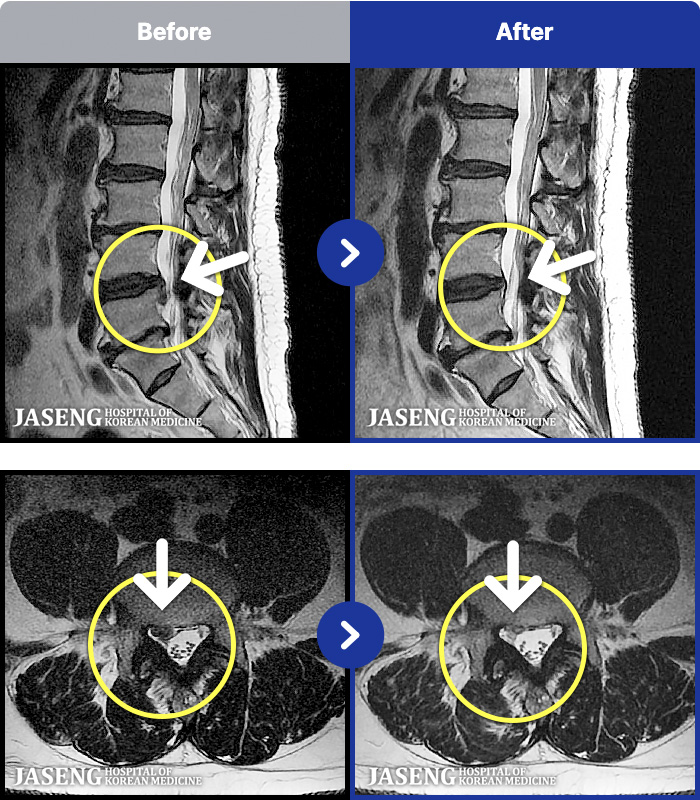

[뱸] 19.11.28~25.05.06